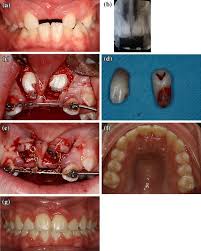

Window technique this represents the simplest form of open exposure. The open exposure technique consists of surgical removal of the tissue covering the tooth, leaving it exposed to the oral cavity. 26,27 in the case shown here, closed eruption was chosen for the impacted central and. Within the different approaches there exist two main options for the subsequent eruption of the impacted teeth (6): Open eruption technique the open eruption technique was the first method used to uncover impacted teeth.

Chaushu s(1), becker a, zeltser r, vasker n, chaushu g. Preorthodontic exposure and autonomous eruption The open exposure technique consists of surgical removal of the tissue covering the tooth, leaving it exposed to the oral cavity. Given the reported success of forced eruption, the technique requires… continue reading The present study provides information to patients and clinicians. Duration of surgical procedure (in min) click here to view Dr vanarsdall recommends open exposure with a repositioned gingival flap (pediculated connective tissue graft) above the impacted canine. Apically position flap the goal is to choose a technique that exposes the canine within the a zone of keratinized mucosa without involvement of the cementoenamel junction 27. The open eruption technique may be performed in two different ways, as described below. If the canine crown is positioned distal to the mesial aspect of the lateral incisor, an open technique is performed. Forced eruption can preserve the natural root system and related periodontal architecture, resulting in years of additional service for the patient. Open eruption through a window; In this technique sufficient space.

If the canine crown is positioned distal to the mesial aspect of the lateral incisor, an open technique is performed open'er. (1) window technique, (2) full flap open procedure, and (3) apically repositioned flap technique.